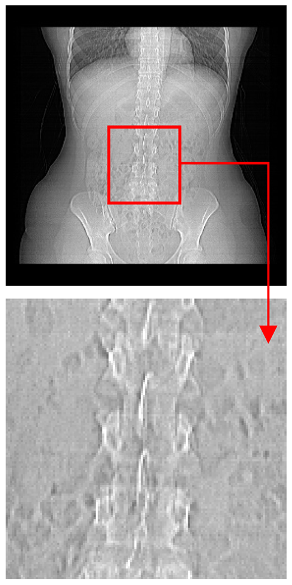

| Original Medical Images | Shadow Images Produced by Using (7,4) Hamming Code (MSBs) | ||

|---|---|---|---|

| Pair 1 | Pair 2 | ||

![]() | ![]() | ![]() | ![]() |

| Pair 3 | Pair 4 | ||

| Shadow images produced by using (15,11) Hamming code (LSBs) | Shadow images produced by using (15,11) Hamming code (MSBs) | ||